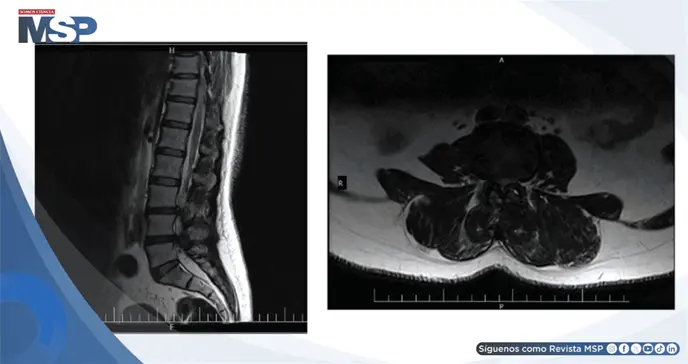

Un hombre con hernia de disco lumbar L4-L5 confirmada por resonancia magnética presentó dolor intenso irradiado a extremidades inferiores tras levantar a su hijo.

La resonancia magnética reveló protrusiones discales en L4-L5 y L3-L4 con abultamiento central. Fue tratado con medicamentos (Mixodin, Nuvazin y Profen) que proporcionaron alivio parcial. Persistieron rigidez y frialdad matutina en la pantorrilla lateral izquierda, que mejoraban tras caminar 5 minutos.